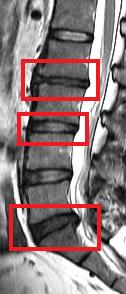

今次的研究是一項以南中國地區人口而作出的具代表性抽樣研究,從上述大型人口群組中抽出21歲或以上的成年人為研究對象。在是次的研究中,研究人員分析了合共2,599位成年人的磁力共振(MRI)檢查數據。當中27%(709人)沒有椎間盤退化,而73%(1,809人)則有椎間盤退化。在患有椎間盤退化的成年人當中,有7%體重過輕,48%體重正常,36%過重和9%肥胖。超重及肥胖的成年人出現椎間盤退化程度及發展成更嚴重的病徵的機會,比正常體重或過輕的成年人嚴重。